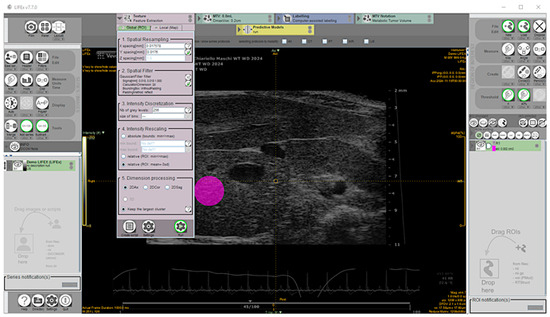

Preclinical Application of Computer-Aided High-Frequency Ultrasound (HFUS) Imaging: A Preliminary Report on the In Vivo Characterization of Hepatic Steatosis Progression in Mouse Models

Metabolic dysfunction-associated steatotic liver disease (MASLD) is one of the most common chronic liver disorders worldwide and can lead to inflammation, fibrosis, and liver cancer. To better understand the impact of an unbalanced hypercaloric diet on liver phenotype in impaired autophagy, the study [...] Read more.

Metabolic dysfunction-associated steatotic liver disease (MASLD) is one of the most common chronic liver disorders worldwide and can lead to inflammation, fibrosis, and liver cancer. To better understand the impact of an unbalanced hypercaloric diet on liver phenotype in impaired autophagy, the study compared C57BL/6J wild type (WT) and MAPK15-ERK8 knockout (KO) male mice with C57BL/6J background fed for 17 weeks with “Western-type” (WD) or standard diet (SD). Liver features were monitored in vivo by high-frequency ultrasound (HFUS) using a semi-quantitative and parametric assessment of pathological changes in the parenchyma complemented by computer-aided diagnosis (CAD) methods. Liver histology was considered the reference standard. WD induced liver steatosis in both genotypes, although KO mice showed more pronounced dietary effects than WT mice. Overall, HFUS reliably detected steatosis-related parenchymal changes over time in the two mouse genotypes examined, consistent with histology. Furthermore, this study demonstrated the feasibility of extracting quantitative features from conventional B-mode ultrasound images of the liver in murine models at early clinical stages of MASLD using a computationally efficient and vendor-independent CAD method. This approach may contribute to the non-invasive characterization of genetically engineered mouse models of MASLD according to the principles of replacement, reduction, and refinement (3Rs), with interesting translational implications. Full article